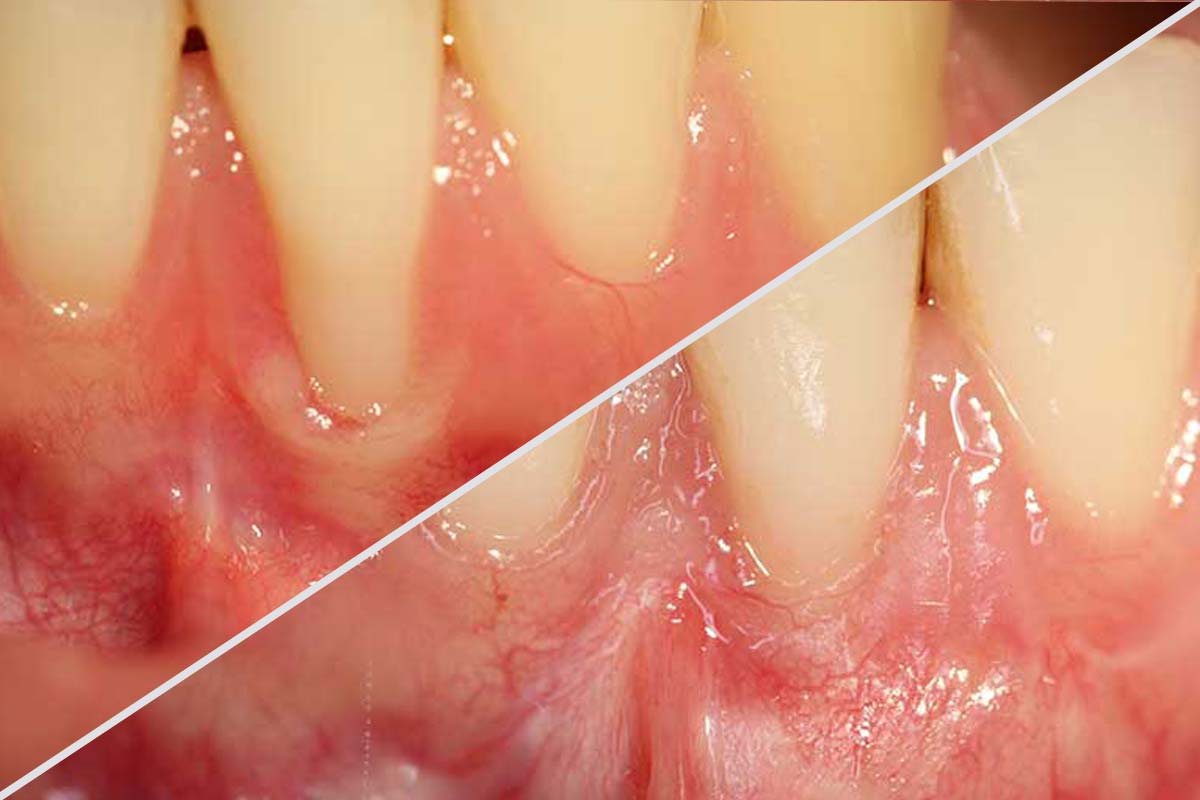

Im Fachartikel von Frau Dr. Schonebeck werden umfassend verschiedene Fallbeispiele zur Rezessionsdeckung vorgestellt. Der Artikel bietet detaillierte Einblicke in moderne Techniken zur Behandlung von Zahnfleischrezessionen und veranschaulicht anhand konkreter Patientenfälle die jeweiligen Vorgehensweisen. Dabei wird nicht nur auf die chirurgischen Methoden, sondern auch auf die individuellen Besonderheiten der einzelnen Fälle eingegangen. Die Fallstudien dienen als praktische Beispiele, um die Komplexität und die spezifischen Herausforderungen der Rezessionsdeckung in unterschiedlichen klinischen Situationen zu verdeutlichen.